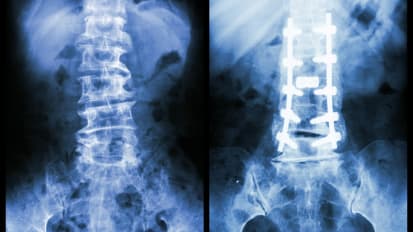

Terrible Triad Injuries and the Complex Elbow: Anatomy and Biomechanics